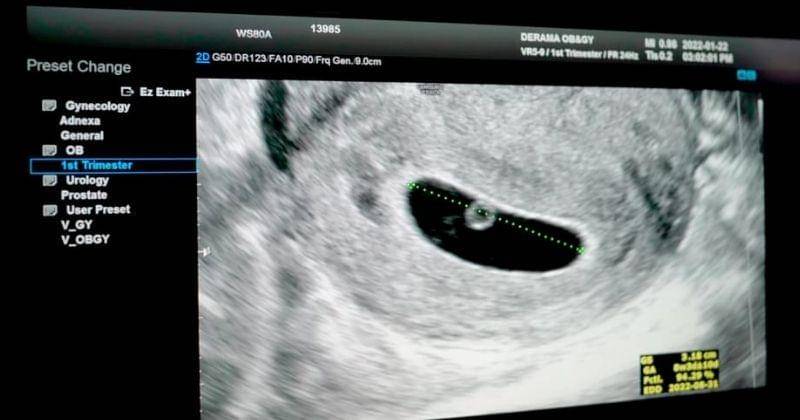

Pada pembukaan episode terbaru kanal JAM2 HOUSE itu, terdengar suara detak jantung bayi dengan latar belakang yang gelap. Kemudian, diikuti dengan Jam Jam mengumumkan kalau ia akan punya adik.

Saat pemeriksaan berlangsung selain melihat ukuran dan bagaimana kondisi adiknya di dalam perut, Jam Jam juga mendengarkan detak jantung adiknya.

Ia bahkan sempat terlihat gugup dan mematung saat mendengarkan suara jantung adiknya dengan baik.

"Suara jantungnya besar sekali," kata Jam Jam pada papanya, Moon Hee Jun.

Karena penasaran, Jam Jam pun memberanikan diri bertanya pada dokter apakah adik berjenis kelamin laki-laki atau perempuan. Sayangnya, dokter pun belum mengetahuinya dan meminta Jam Jam untuk menunggu sedikit lagi.